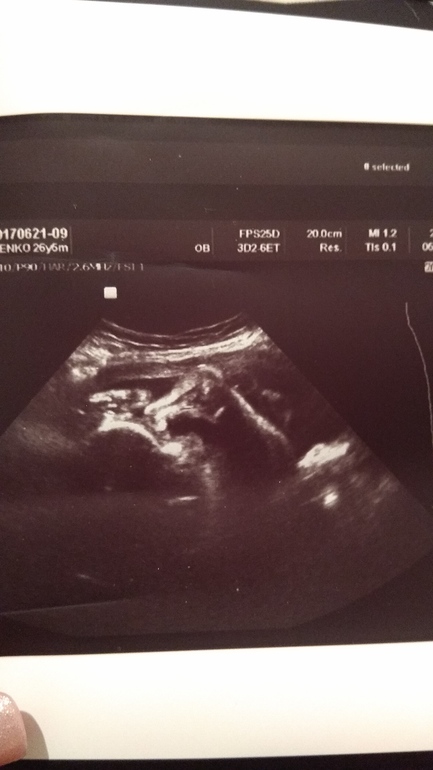

Всё у нас хорошенько, как опережали, так и продолжаем в том же духе. Головастик у нас растет и на попе спокойненько сидит, но после утренних попыток выбраться с меня через мой бок я не удивлена, что перевернулся на попу

Божечки, какой он сладкий присладки, перед узи я сьела мароженку, а он так причмокивал и язычок высовывал, наверное ему тоже понравилось

. Во время узи с врачом и поговорили, и посмеялись, дала пару фоток, делюсь с вами, ну и параметры на память